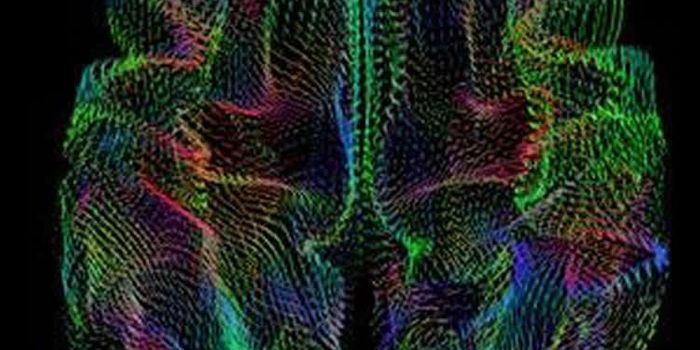

MAR 01, 2016NeuroscienceThe vast network of neurons, dendrites, axons and other hardware that is responsible for sending messages all over the b ...